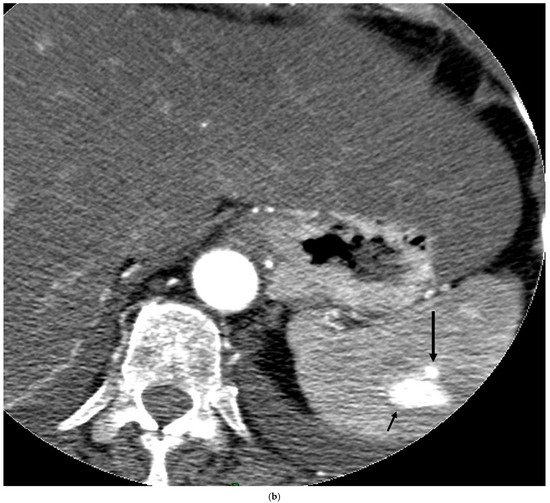

- Boukobza, M.; Ilic-Habensus, E.; Arregle, F.; Habib, G.; Duval, X.; Laissy, J.P. Hepatic artery aneurysms in infective endocarditis: Report of 10 cases and literature review. Ann. Vasc. Surg. 2024, 105, 252–264. [Google Scholar] [CrossRef]